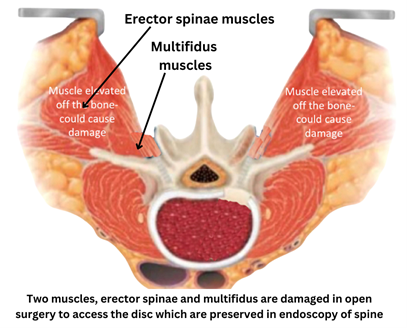

Muscles: Variable degree of damage occurs to two important muscles, erector spinae and multifidus muscle. Erector spinae is a ‘movement muscle’ that enable us to stand erect. Damage to this muscle causes stooped posture, slouching and secondary degeneration of spine and pain. Multifdus is a ‘stability muscle’. It keeps you vertebrae stable when the spine is moving, like when we lift a weight or perform any activity that involves back movement. Damage to multifidus muscle allows unsynchronised movements to occur causing secondary degeneration of spine and long term pain.